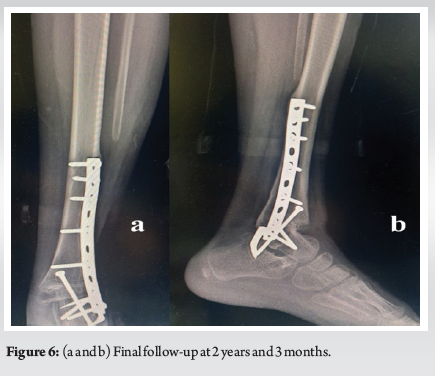

Management of Ewing Sarcoma of Distal Fibula in Child: A Case Report

Wajdi Chermiti , Mohamed Khiareddine , Amir Mhiri , Mourad Mtaoumi , Mahmoud Ben Maitigue , Karim Bouattour ………………………………p.35-40